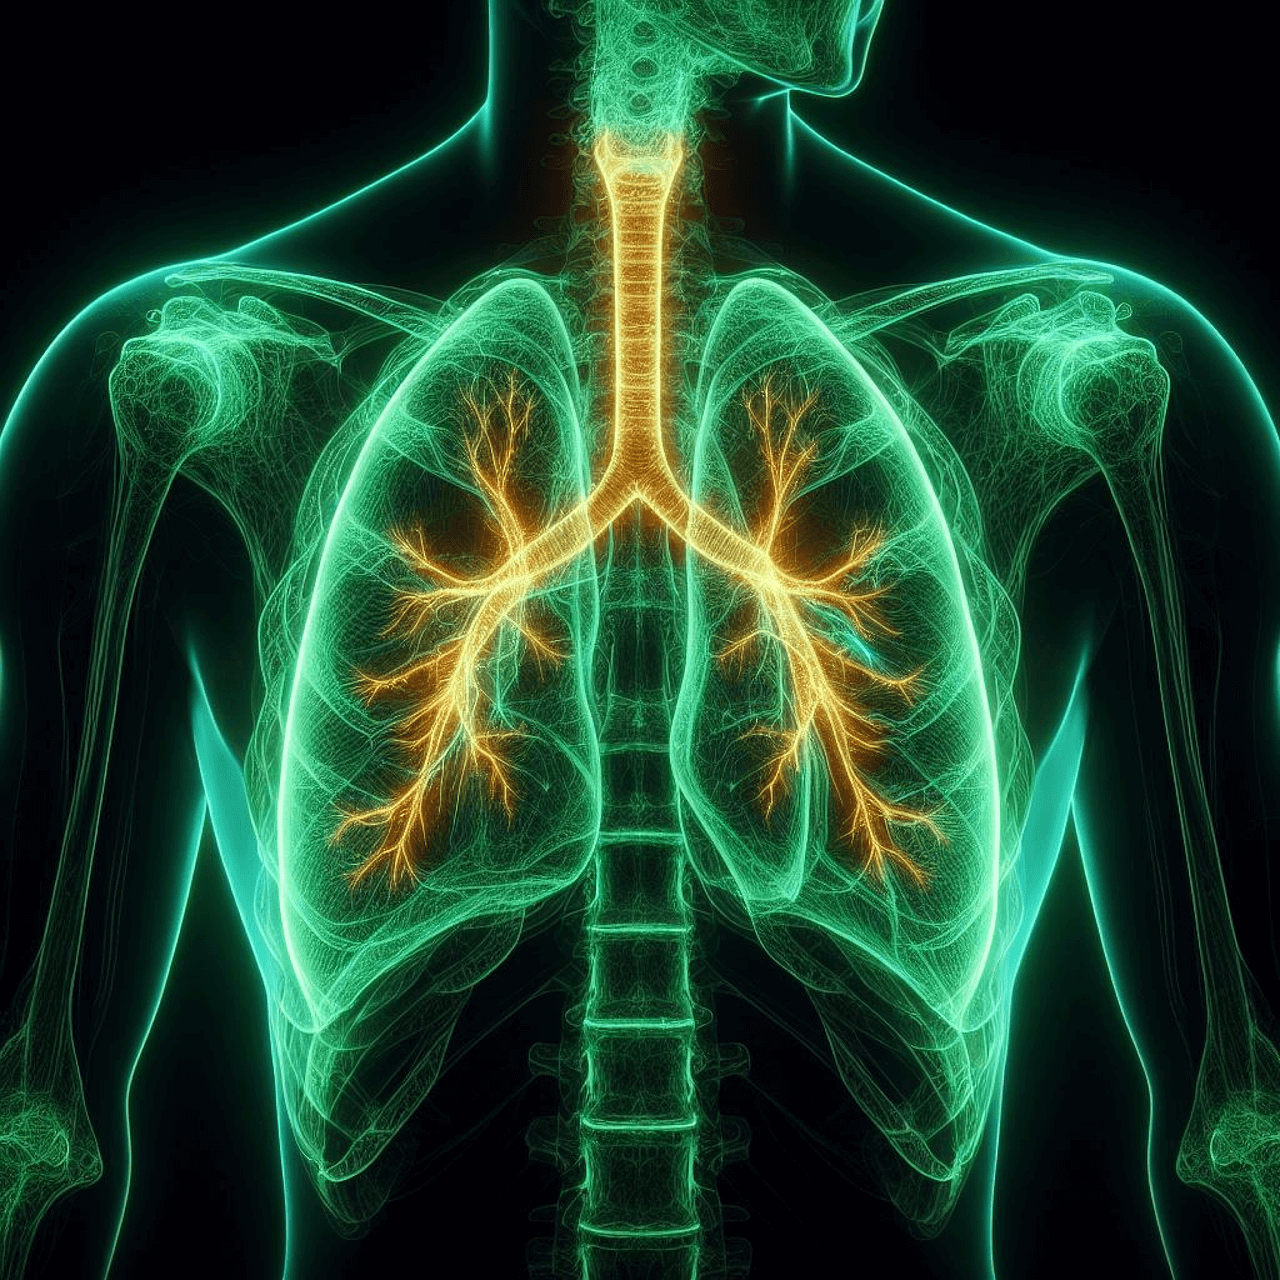

3. 폐암 조기 진단 방법

3-1. 저선량 흉부 CT 검사 (LDCT)

가장 효과적인 조기 진단 방법으로, 1cm 이하의 작은 종양도 확인이 가능합니다. 고위험군(55~74세, 30갑년 이상 흡연자)은 1~2년 간격 검진이 권장됩니다.

3-2. 흉부 X선

일반 건강검진에 포함되지만, 초기 폐암은 발견률이 낮기 때문에 CT와 병행해야 합니다.